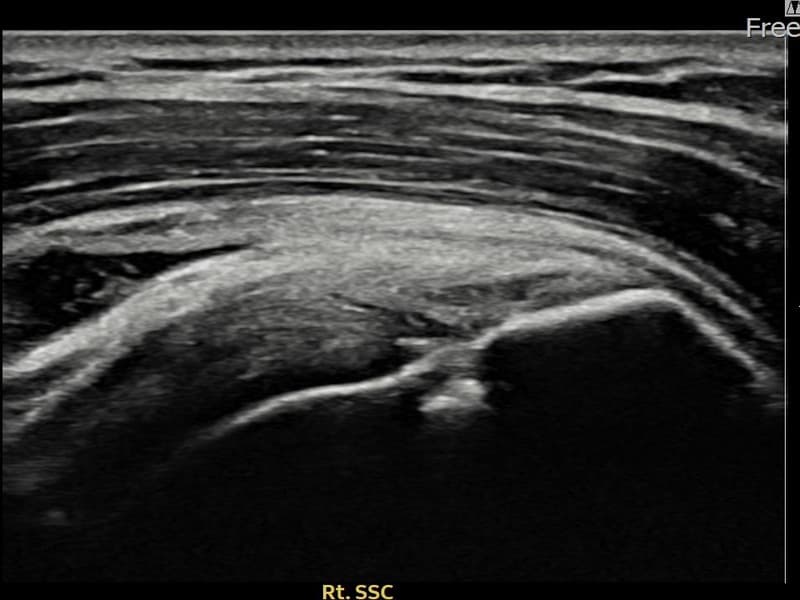

시술 전 초음파 측정 결과 파열 크기는 7mm × 3mm (힘줄 두께의 약 32% 결손)로 확인되었습니다. 시술 전 초음파에서 우측 극하근건 관절면측의 에코 단절과 힘줄 결손 소견이 확인되었습니다. 시술 후 초음파에서 파열 부위에 재생 조직이 형성되고 힘줄 연속성이 회복된 것이 관찰되었습니다.

30대 후반 남성 환자분으로, 우측 어깨 후방 통증이 수개월째 지속되어 내원하셨습니다. 팔을 뒤로 젖히거나 외회전할 때 심한 통증이 있어 운동이나 스포츠 활동에 큰 제약이 있으셨습니다. 초음파 검사에서 우측 극하근건 관절면측 부분파열이 확인되었으며, 초음파 유도 하 축소봉합술을 시행하였습니다. 시술 후 보조기 착용과 단계적 재활 운동을 통해 회복을 진행하였고, 시술 11주 후 추적 초음파에서 힘줄 연속성이 회복되고 외회전 기능이 정상화된 것이 확인되어 스포츠 활동에 복귀하셨습니다.